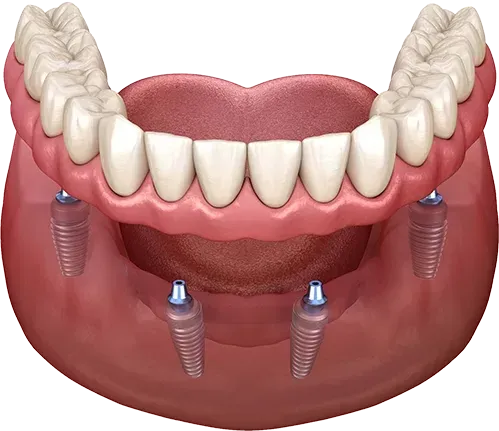

Această procedură implică inserarea unui număr de implanturi dentare (4, 6 sau 8) în cavitatea bucală. Numărul exact de implanturi este determinat de către medicul chirurg, în funcție de evaluarea clinică, de structura osoasă și de cerințele individuale ale pacienților.

Inserarea a 4 implanturi pentru stabilitatea totală a lucrării

Inserarea a 6 implanturi pentru stabilitatea totală a lucrării